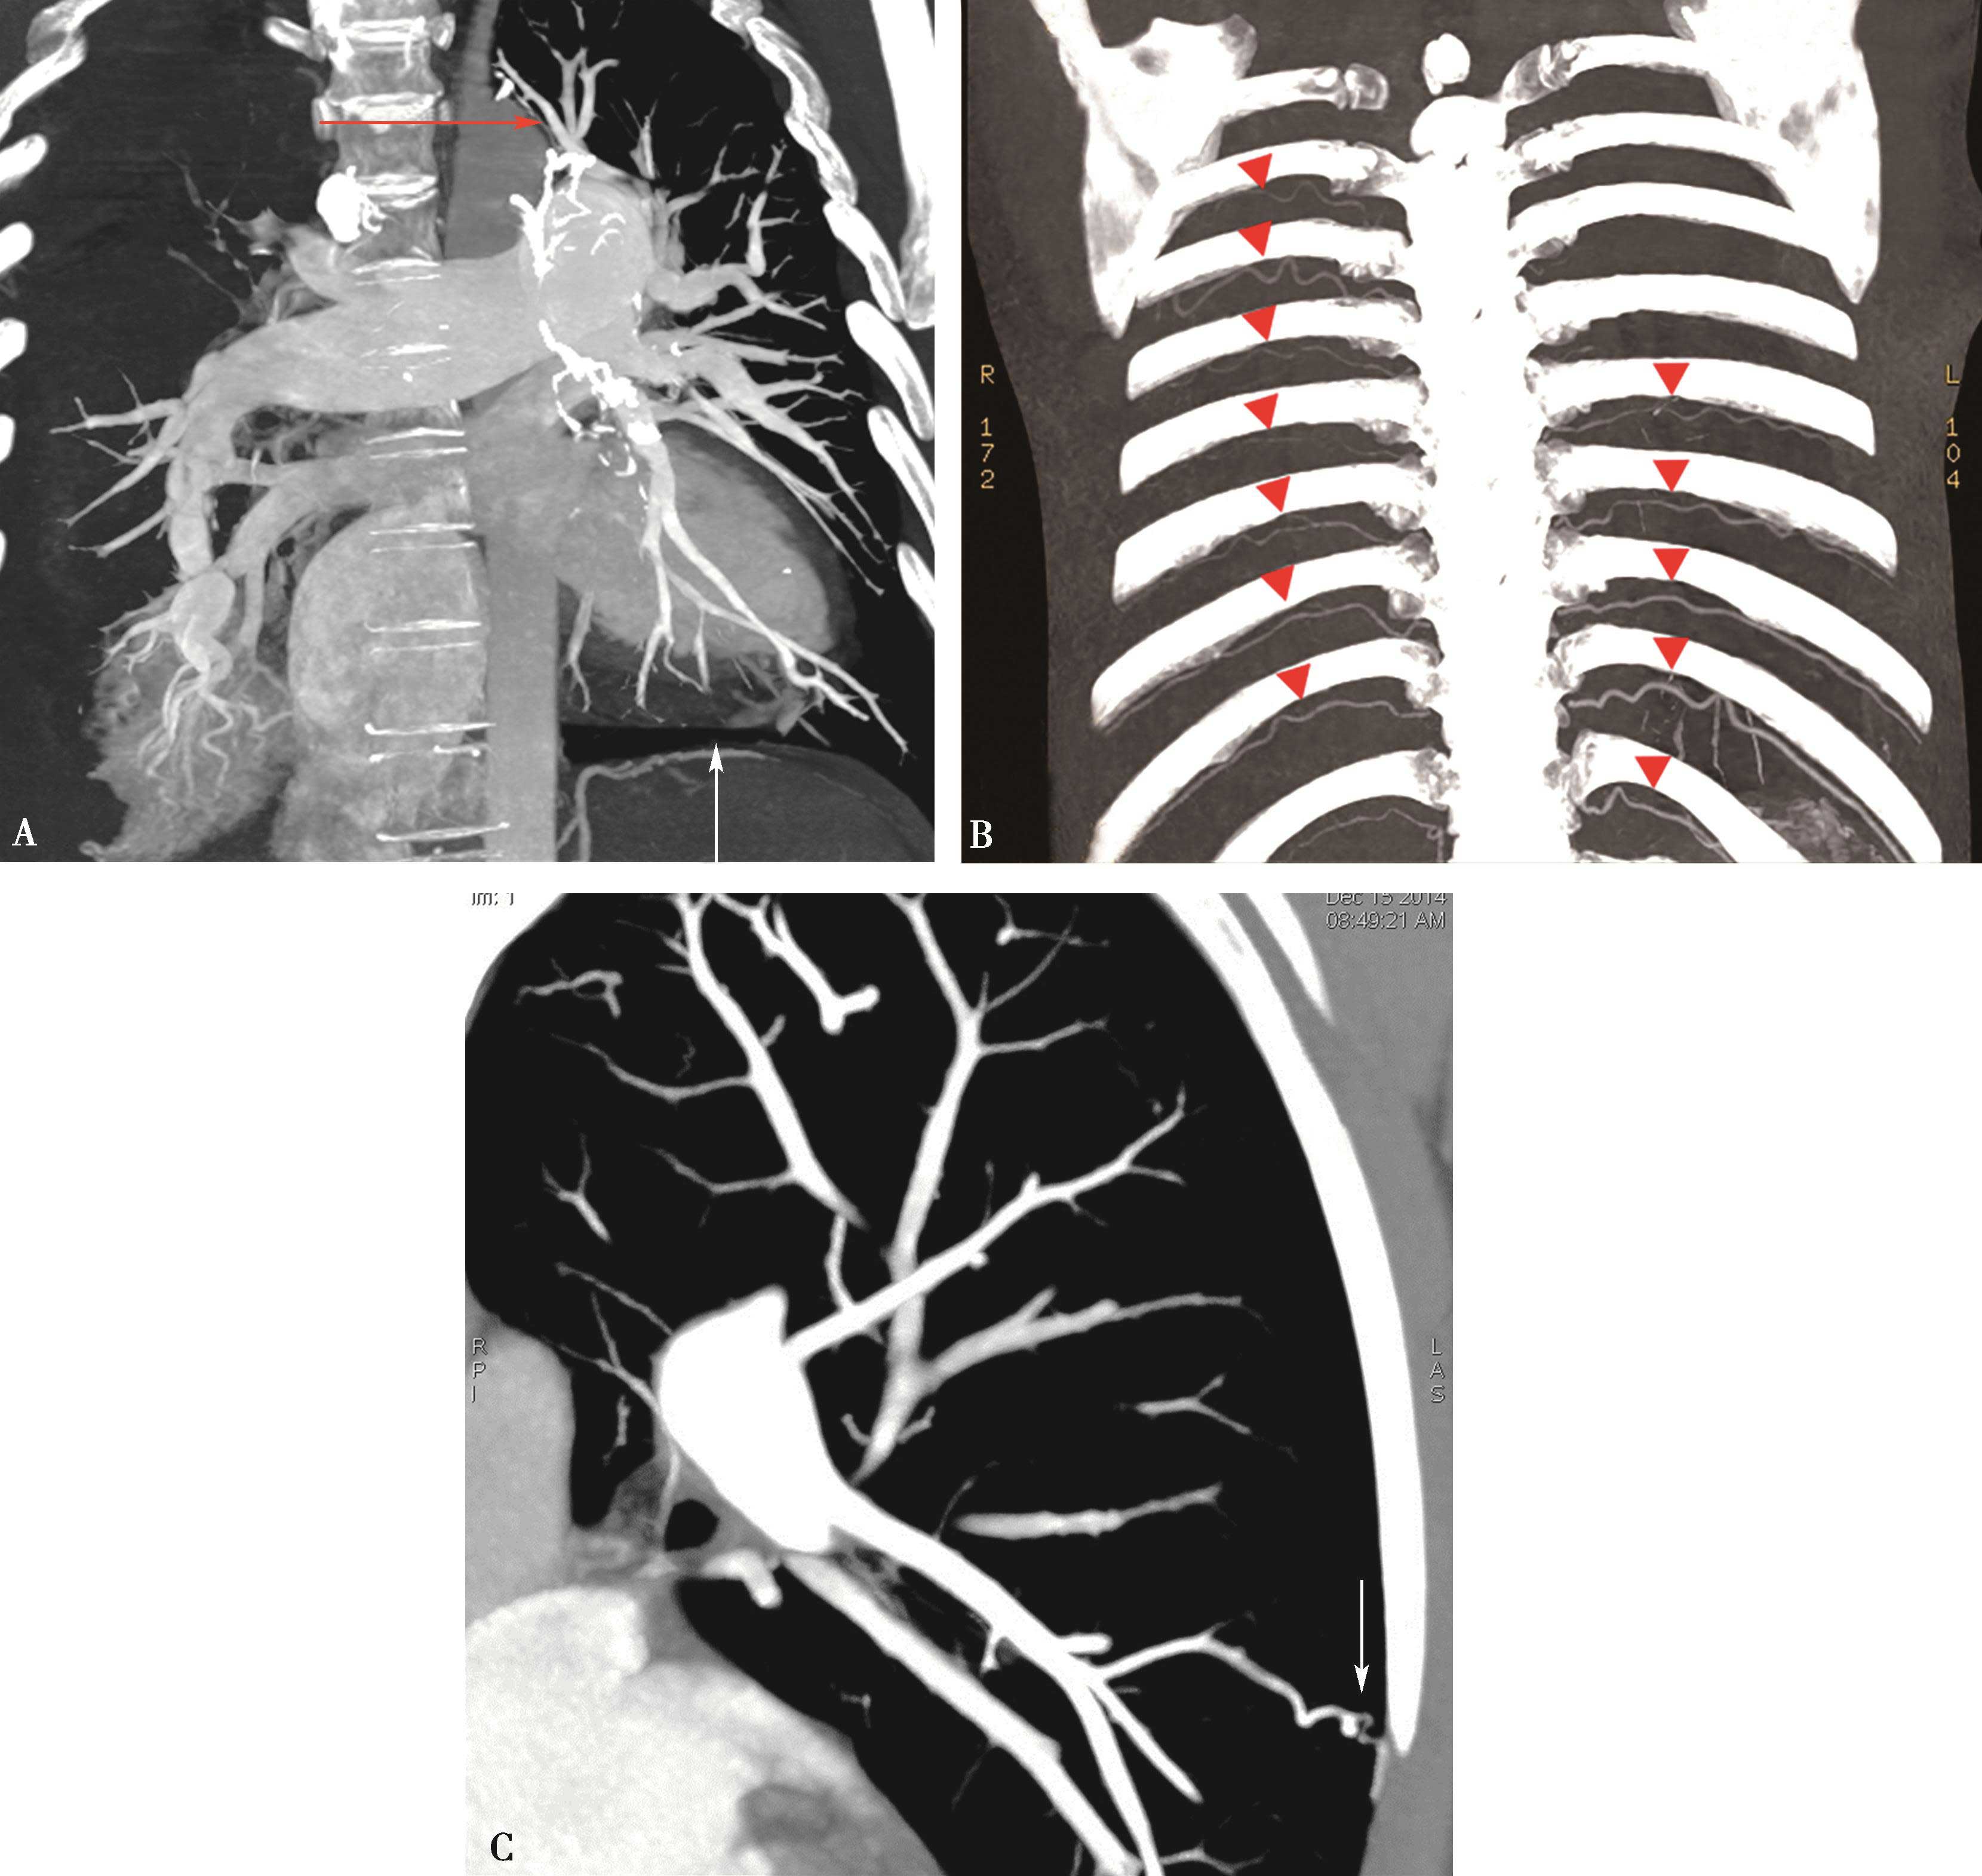

(四)侧支循环系统

随CTEPH肺血管阻塞的加重,支气管动脉血流可随之增加,且可导致经胸膜的侧支循环(如:肋间动脉)进一步开放(图8-4-24A)。一般情况下,支气管动脉只供应支气管营养而不参与气体交换。然而在病理条件,由于肺循环血量的显著降低,支气管动脉血量增加并可参与氧气交换。正常支气管动脉血流约是心输出量的1%~2%。在CTEPH患者,支气管血流约是心输出量的30%。异常扩张迂曲的支气管动脉(直径超过2mm)(图8-4-24B)是肺支气管动脉扩张 的特征性CT表现。

图8-4-24 慢性血栓栓塞性肺动脉高压,侧支循环,可见支气管动脉、肋间动脉-乳内动脉(B▼)、膈下动脉(A↑);C.肋间动脉经胸膜与肺动脉末梢构成侧支(C↑)

最近的一项研究提示,CTEPH(73%)与特发性肺动脉高压(14%)患者相比异常扩大的支气管和非支气管动脉出现频率更高,这些发现有助于鉴别这两种病理状态。最常见的异常非支气管动脉包括膈下、肋间和乳内动脉(见图 8-4-24)。